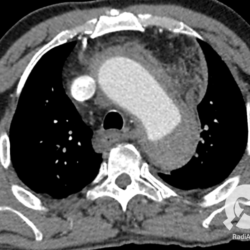

Paciente com dor torácica súbita, realizou esta tomografia que revelou um aneurisma de aorta ascendente, porém com uma particularidade grave: existe uma imagem linear na luz aórtica que corresponde a uma dissecção da camada íntima formando uma falsa luz no vaso. Na maioria das vezes, a falsa luz tem calibre maior e fluxo mais lento.